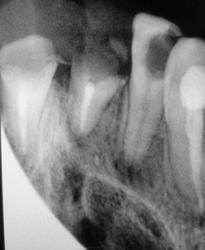

На перелом корня похоже?

Скиалогия, проекционное наложение 3-го корня.

Так в том зубике третий корень не предусмотрен...

На этом снимке видно, что здесь 3 корня : один медиальный и два дистальных ( язычный и щечный)

Продолный перелом одного из корней.

Здравствуйте уважаемый Валентин Львович! smiley  В таком случае, требуется очный осмотр : потрогать, пошевелить,  постучать и т. д.  Продольный перелом корня по снимку увидеть весьма  проблематично.  Скорее соглашусь с Евгением  Алексеевичем – здесь проекционное наложение корня.

Что, линия перелома не видна?

Конусно-лучевую компьютерную томографию (КЛКТ) нужно провести в таком случае))))